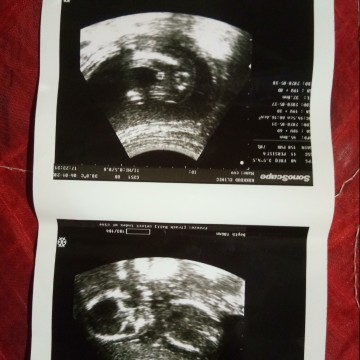

ขอดูรูปหน่อย...เห็นจู๋ชัดมาก...19สัปดาห์ แอบหวังเล็กๆว่าจะได้ลูกสาว.. แต่หมอบอก90%ผู้ชาย...แถมเห็นจู๋อีก